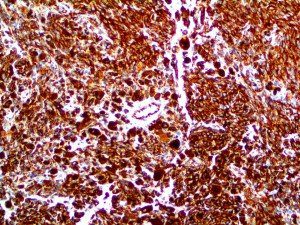

It is the ICU physician who is most likely to witness one of the deadliest manifestations of the abnormal immunological response, the cytokine storm syndrome (CSS). This response is also referred to by some as the cytokine release syndrome (CRS). CSS is characterized by continuous activation and expansion of macrophage and lymphocyte populations, which secrete large amounts of cytokines, causing the cytokine storm. This massive cytokine release is akin to hemophagocytic lymphohistiocytosis (HLH) disease, a syndrome characterized by initial unchecked and persistent activation of cytotoxic T lymphocytes and NK cells.

Clinical and laboratory manifestations of HLH include fever, enlarged liver and/or spleen, neurologic dysfunction, coagulopathy, liver dysfunction, cytopenias (i.e., low levels of erythrocytes, leukocytes, and/or platelets), hypertriglyceridemia, hyperferritinemia, hemophagocytosis, and eventually diminished NK cell activity as the immune system becomes progressively paralyzed. HLH can be familial (primary HLH) or secondary to another disease process (sHLH), such as rheumatic disease, in which it is referred to as macrophage activation syndrome (MAS, characterized by elevated ferritin).